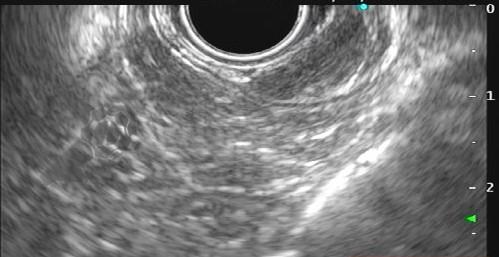

Figuras 1 e 2. Imagem endoscópica em visão direta de lesão protrusa entre pequena curvatura e parede posterior de corpo gástrico proximal, revestida por mucosa com superfície regular, normocorada e íntegra. A imagem ecoendoscópica demonstra lesão com ecogenicidade hipoecoica, ecotextura homogênea, formato ovalado, sem características internas, sem vascularização ao doppler, limites precisos, contornos regulares, medindo aproximadamente 20 x 6 mm e inserida em camada muscular própria. Punções ecoguiadas foram realizadas com agulha FNB, sendo o anatomopatológico e imuno-histoquímica compatíveis com GIST gástrico. Fonte: arquivos do Instituto do Câncer do Estado de São Paulo (ICESP/HCFMUSP)Figuras 1 e 2. Imagem endoscópica em visão direta de lesão protrusa entre pequena curvatura e parede posterior de corpo gástrico proximal, revestida por mucosa com superfície regular, normocorada e íntegra. A imagem ecoendoscópica demonstra lesão com ecogenicidade hipoecoica, ecotextura homogênea, formato ovalado, sem características internas, sem vascularização ao doppler, limites precisos, contornos regulares, medindo aproximadamente 20 x 6 mm e inserida em camada muscular própria. Punções ecoguiadas foram realizadas com agulha FNB, sendo o anatomopatológico e imuno-histoquímica compatíveis com GIST gástrico. Fonte: arquivos do Instituto do Câncer do Estado de São Paulo (ICESP/HCFMUSP)Figuras 3 e 4. Imagem endoscópica em visão direta de abaulamento de parede em segunda porção duodenal distalmente à papila duodenal maior, revestida por mucosa com íntegra, de coloração amarelada e superfície regular. A ecoendoscopia demonstra lesão com ecogenicidade hiperecoica, ecotextura homogênea, formato arredondado, medindo cerca de 10 mm no maior eixo, com limites precisos, contornos regulares, medindo cerca de 10 mm no maior diâmetro e inserida em camada submucosa, sendo os achados endoscópicos e ecoendoscópicos compatíveis com lipoma.Figuras 3 e 4. Imagem endoscópica em visão direta de abaulamento de parede em segunda porção duodenal distalmente à papila duodenal maior, revestida por mucosa com íntegra, de coloração amarelada e superfície regular. A ecoendoscopia demonstra lesão com ecogenicidade hiperecoica, ecotextura homogênea, formato arredondado, medindo cerca de 10 mm no maior eixo, com limites precisos, contornos regulares, medindo cerca de 10 mm no maior diâmetro e inserida em camada submucosa, sendo os achados endoscópicos e ecoendoscópicos compatíveis com lipoma.Fig. 5. Imagem endoscópica em visão direta de lesão protrusa em parede anterior de antro gástrico proximal, revestida por mucosa normocorada, com superfície regular, sendo sugestiva de lesão subepitelial.Fig. 6. A ecoendoscopia evidencia lesão com ecogenicidade hipoecoica, ecotextura predominantemente homogênea, formato arredondado, limites precisos, bordos regulares, medindo aproximadamente 13,4 x 12 mm, sem focos hiperecoicos ou calcificações no interior e inserida na camada muscular própria. Punções ecoguiadas foram realizadas com agulha FNB, sendo anatomopatológico e imuno-histoquímica confirmando schwanomma gástrico.Fig. 7 e 8. Imagem de esofagogastroduodenoscopia demonstra lesão protrusa em papila duodenal maior revestida por mucosa enantemática e com superfície com três erosões recobertas por fibrina.Fig. 7 e 8. Imagem de esofagogastroduodenoscopia demonstra lesão protrusa em papila duodenal maior revestida por mucosa enantemática e com superfície com três erosões recobertas por fibrina.Fig. 9 e 10. Imagem à ecoendoscopia demonstra lesão com formato ovalado, ecogenicidade hipoecoica, ecotextura heterogênea, com contornos regulares, sem adenopatia adjacente, sem vascularização ao doppler, sem características internas, medindo cerca de 20 x 11 x 24 mm, inserida na camada submucosa, não havendo acometimento da muscular própria. Foram realizadas punções ecoguiadas com agulha FNA 22 gauge, sendo o anatomopatológico e imunohistoquímica compatíveis com tumor neuroendócrino de papila duodenal bem diferenciado grau 1.Fig. 9 e 10. Imagem à ecoendoscopia demonstra lesão com formato ovalado, ecogenicidade hipoecoica, ecotextura heterogênea, com contornos regulares, sem adenopatia adjacente, sem vascularização ao doppler, sem características internas, medindo cerca de 20 x 11 x 24 mm, inserida na camada submucosa, não havendo acometimento da muscular própria. Foram realizadas punções ecoguiadas com agulha FNA 22 gauge, sendo o anatomopatológico e imunohistoquímica compatíveis com tumor neuroendócrino de papila duodenal bem diferenciado grau 1.Fig. 11 e 12. Esofagogastroduodenoscopia demonstra abaulamento de parede anterior de corpo gástrico proximal, com mucosa normocorada, superfície regular com depressão central, sendo compatível com lesão subepitelialFig. 11 e 12. Esofagogastroduodenoscopia demonstra abaulamento de parede anterior de corpo gástrico proximal, com mucosa normocorada, superfície regular com depressão central, sendo compatível com lesão subepitelialFig. 13 e 14. Ecoendoscopia demonstrou formação com ecogenicidade hipoecoica, ecotextura homogênea, formato ovalado, limites bem definidos, contornos regulares, medindo aproximadamente 13 mm e inserida na camada submucosa. Lesão foi submetida a ressecção endoscópica transmural com dispositivo FTRD. A histopatologia e imunohistoquímica confirmaram TNE gástrico bem diferenciado grau 2.Fig. 13 e 14. Ecoendoscopia demonstrou formação com ecogenicidade hipoecoica, ecotextura homogênea, formato ovalado, limites bem definidos, contornos regulares, medindo aproximadamente 13 mm e inserida na camada submucosa. Lesão foi submetida a ressecção endoscópica transmural com dispositivo FTRD. A histopatologia e imunohistoquímica confirmaram TNE gástrico bem diferenciado grau 2.